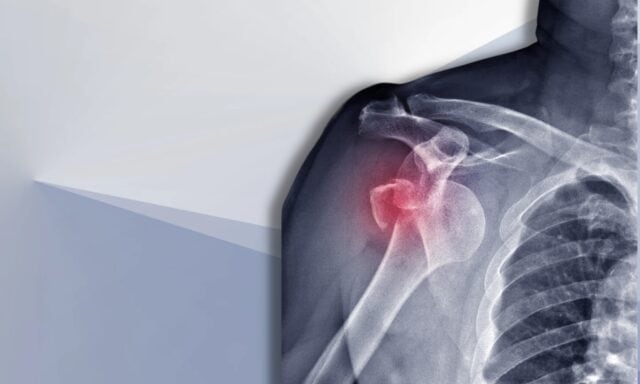

Épaule instable

Dans cet épisode, nous allons parler de tout ce qui concerne l'instabilité de l'épaule. Vous en saurez plus sur la classification de Stanmore et sur les dommages structurels après une dislocation. Nous discuterons du patient type souffrant d'instabilité de l'épaule et de la manière dont se déroule un examen. Nous aborderons les schémas d'activation musculaire, la chirurgie et la manière dont pourrait se présenter la prise en charge physiothérapeutique d'un patient souffrant d'instabilité de l'épaule. Alors assurez-vous d'écouter l'épisode complet !